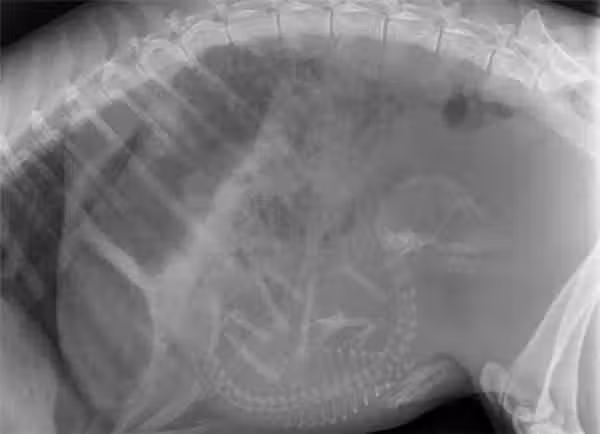

12.鯊魚的X光照,由於是卵胎生,里頭的寶寶已經很有殺手范了